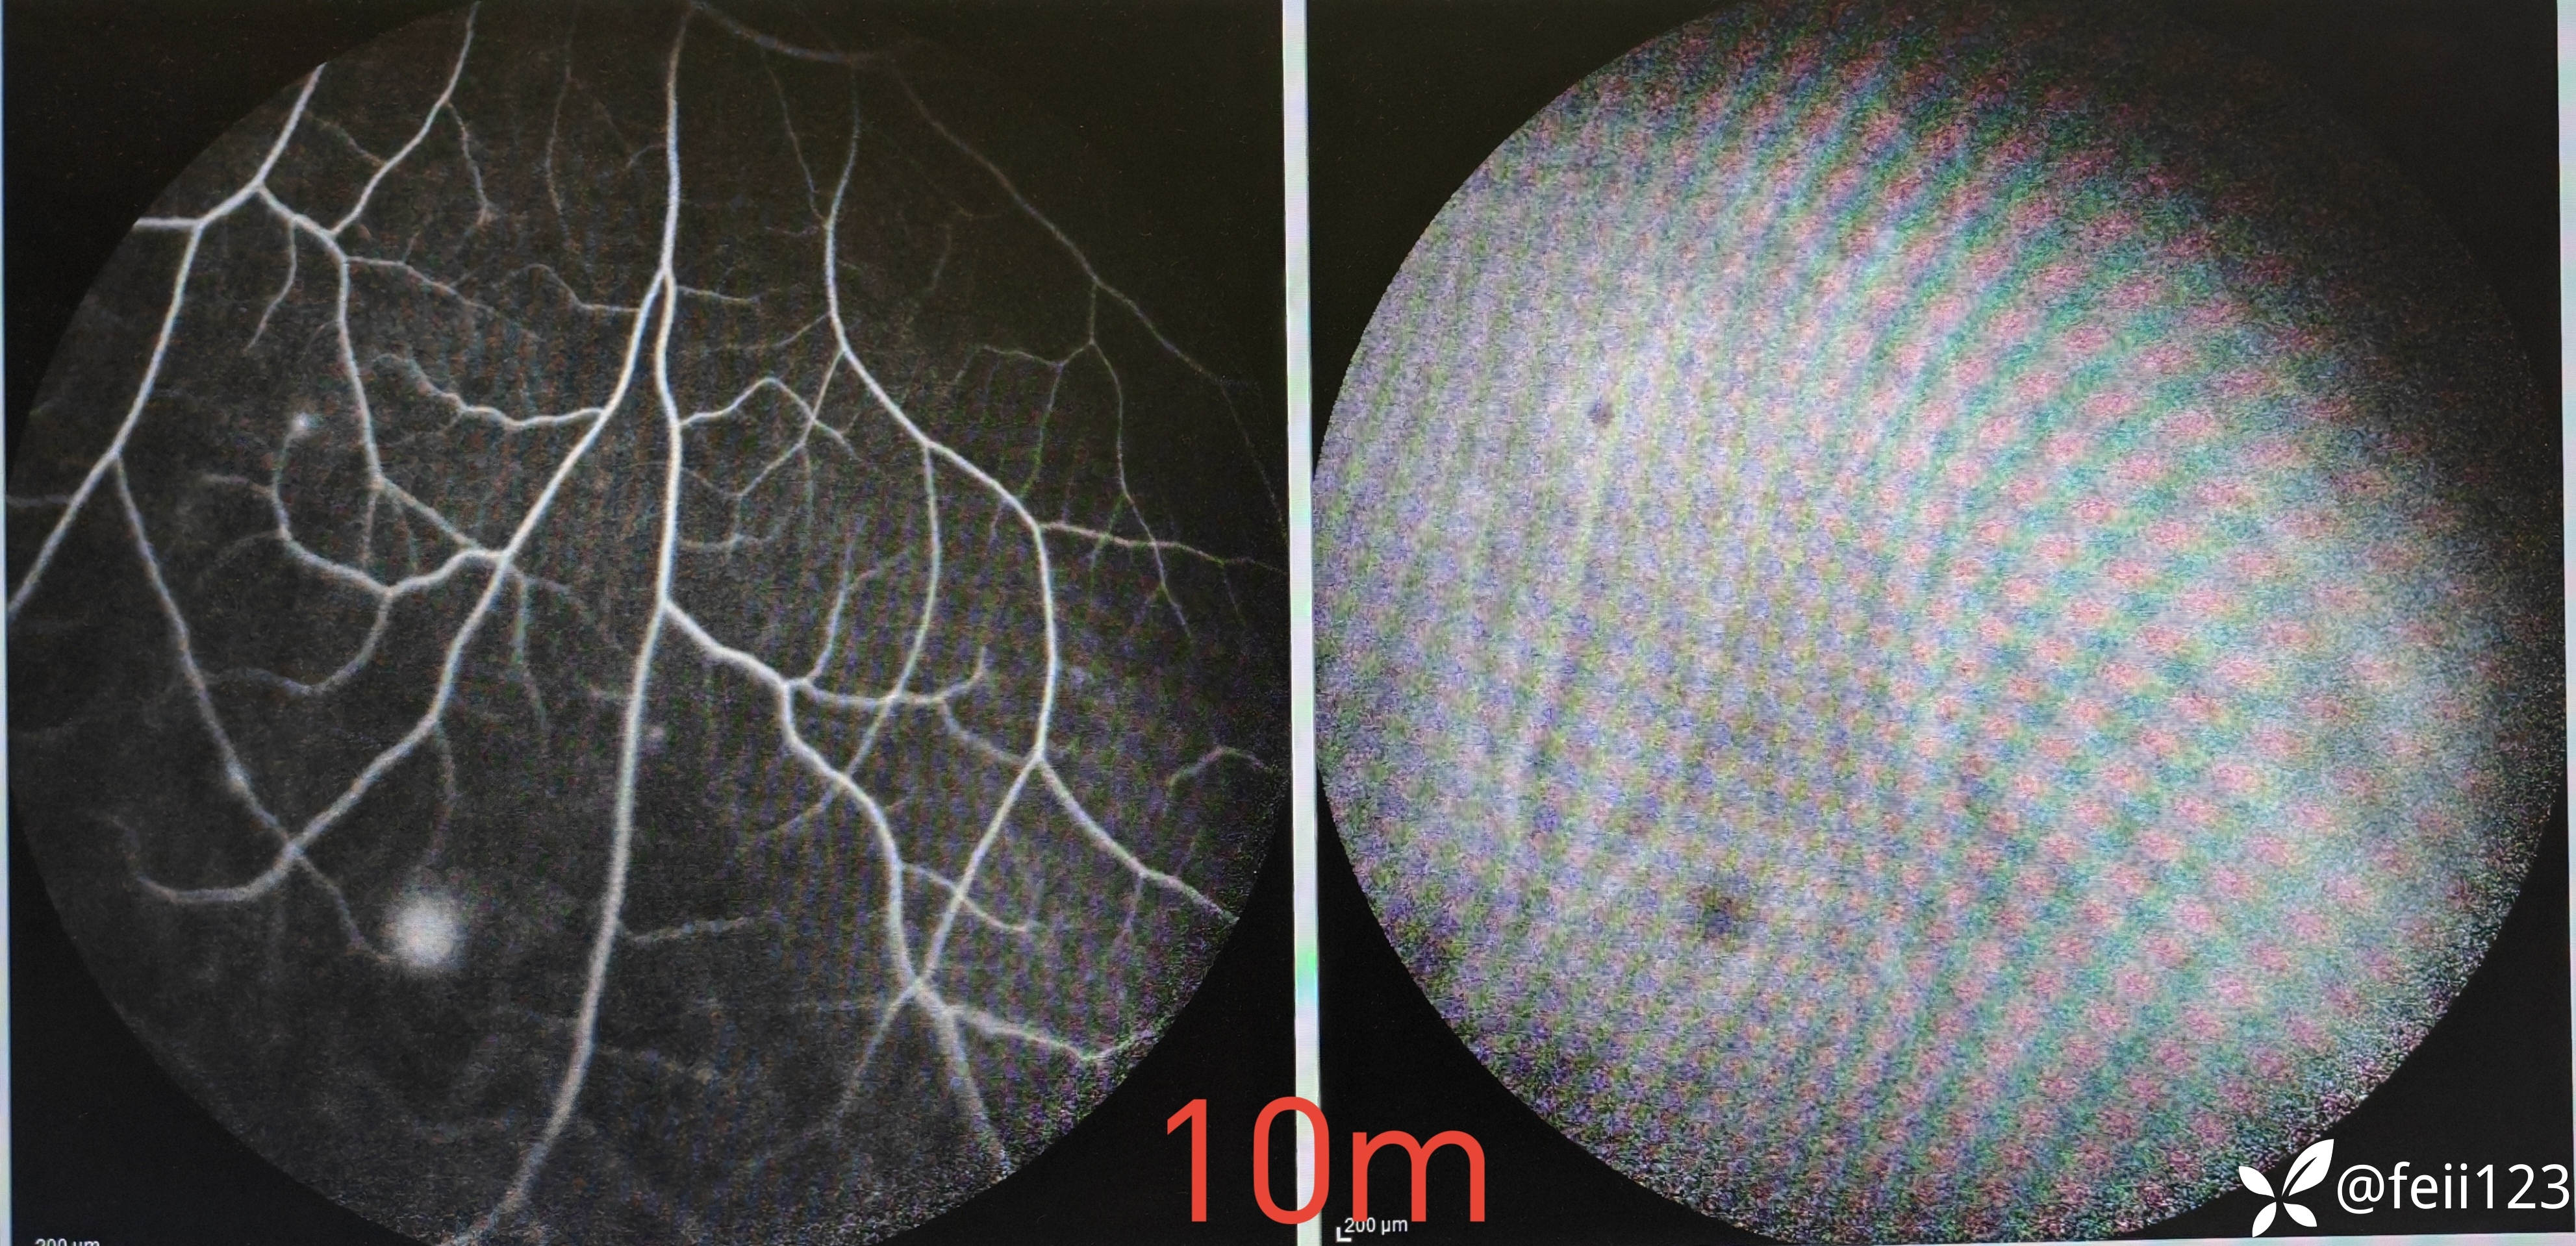

患者信息】:年轻男性30岁

【主诉】:左眼前黑点5天,无诉闪光感

【现病史及既往史】:无特殊,无全身病,中高度近视史

【检查】矫正视力右眼1.0左眼0.4,眼压正常15 16,眼前段未见异常,玻璃体清,眼底如图,左眼底可见后极部及鼻侧周边多个白点。